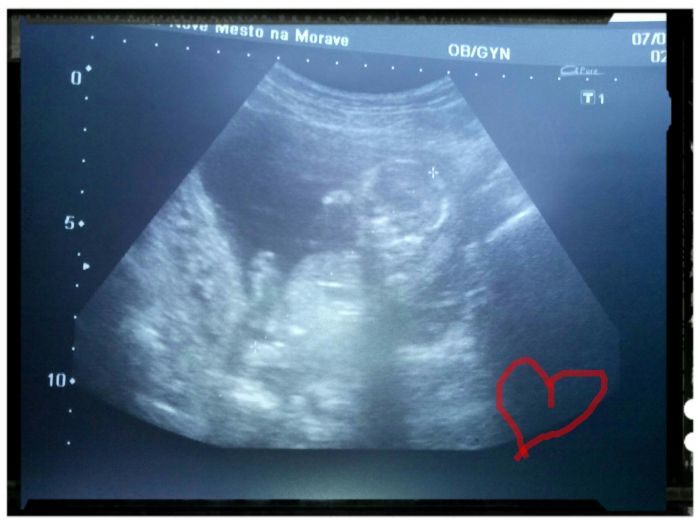

Tak jsme v poradku :)) nedalo mi to jsem hrozna ae predevcirem jsem spadla ze zidle a mela jsem o malou strach :( jsem 14+2 a mame skoro 9 cm